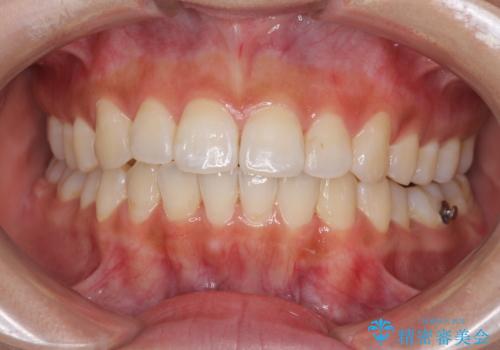

前歯のデコボコが気になる インビザラインによる矯正治療

- 上下前歯のデコボコを気にして来院された患者様です。

インビザラインによる上下歯列の拡大と、IPR(歯と歯の間を削る)にるスペースの獲得により、前歯のデコボコを改善することとしました。

しっかりと装着時間を遵守してくださったので、思い通りの歯列に整えることができました。

結婚式前に終了させることができ、患者様には大変満足していただきました。